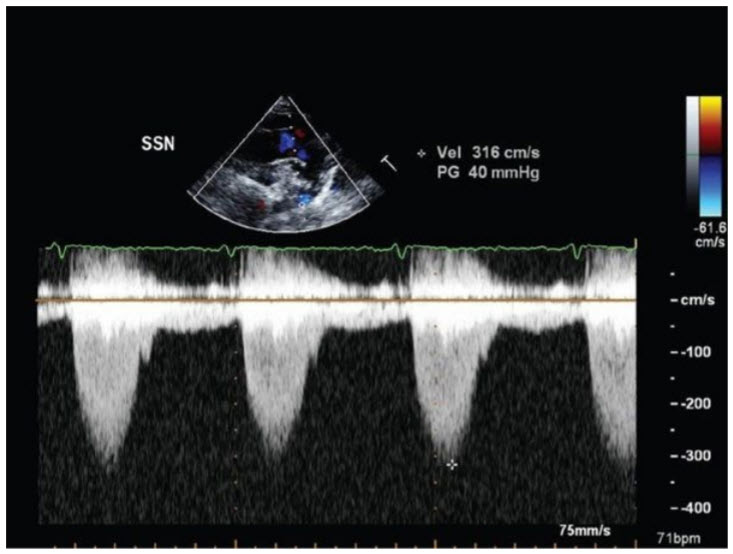

Which of the following statements is correct regarding the echocardiographic image from this patient obtained from the suprasternal notch (figure below).

A. Pressure gradients are usually underestimated using the simplified Bernoulli equation

B. Pressure gradients are usually accurate using the simplified Bernoulli equation

C. Pressure gradients shown are not consistent with severe coarctation

D. Presence of systolic and diastolic flow is consistent with severe coarctation